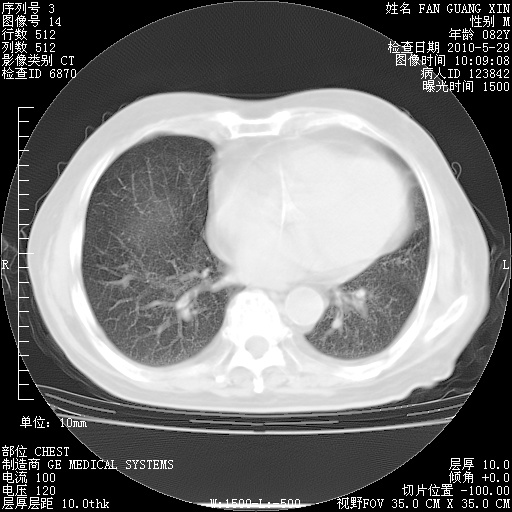

再治疗10天后的肺部CT 纵膈窗

阅读此次胸部CT,肺间质渗出性改变较入院时有吸收。目前从体温、白细胞、中性分叶明显增高,肯定存在细菌感染(发生医院感染哦,若无消化道及泌尿系统等感染的依据,肺部感染可能大)。若你院头孢哌酮舒巴坦钠耐药率较高,同意你的方案,若48小时体温仍高,可考虑使用碳青霉稀类抗菌药物,同时可予超声雾化、注意滴数时加大液体量。白蛋白33.30g/L较低哦,需加强营养等支持治疗。